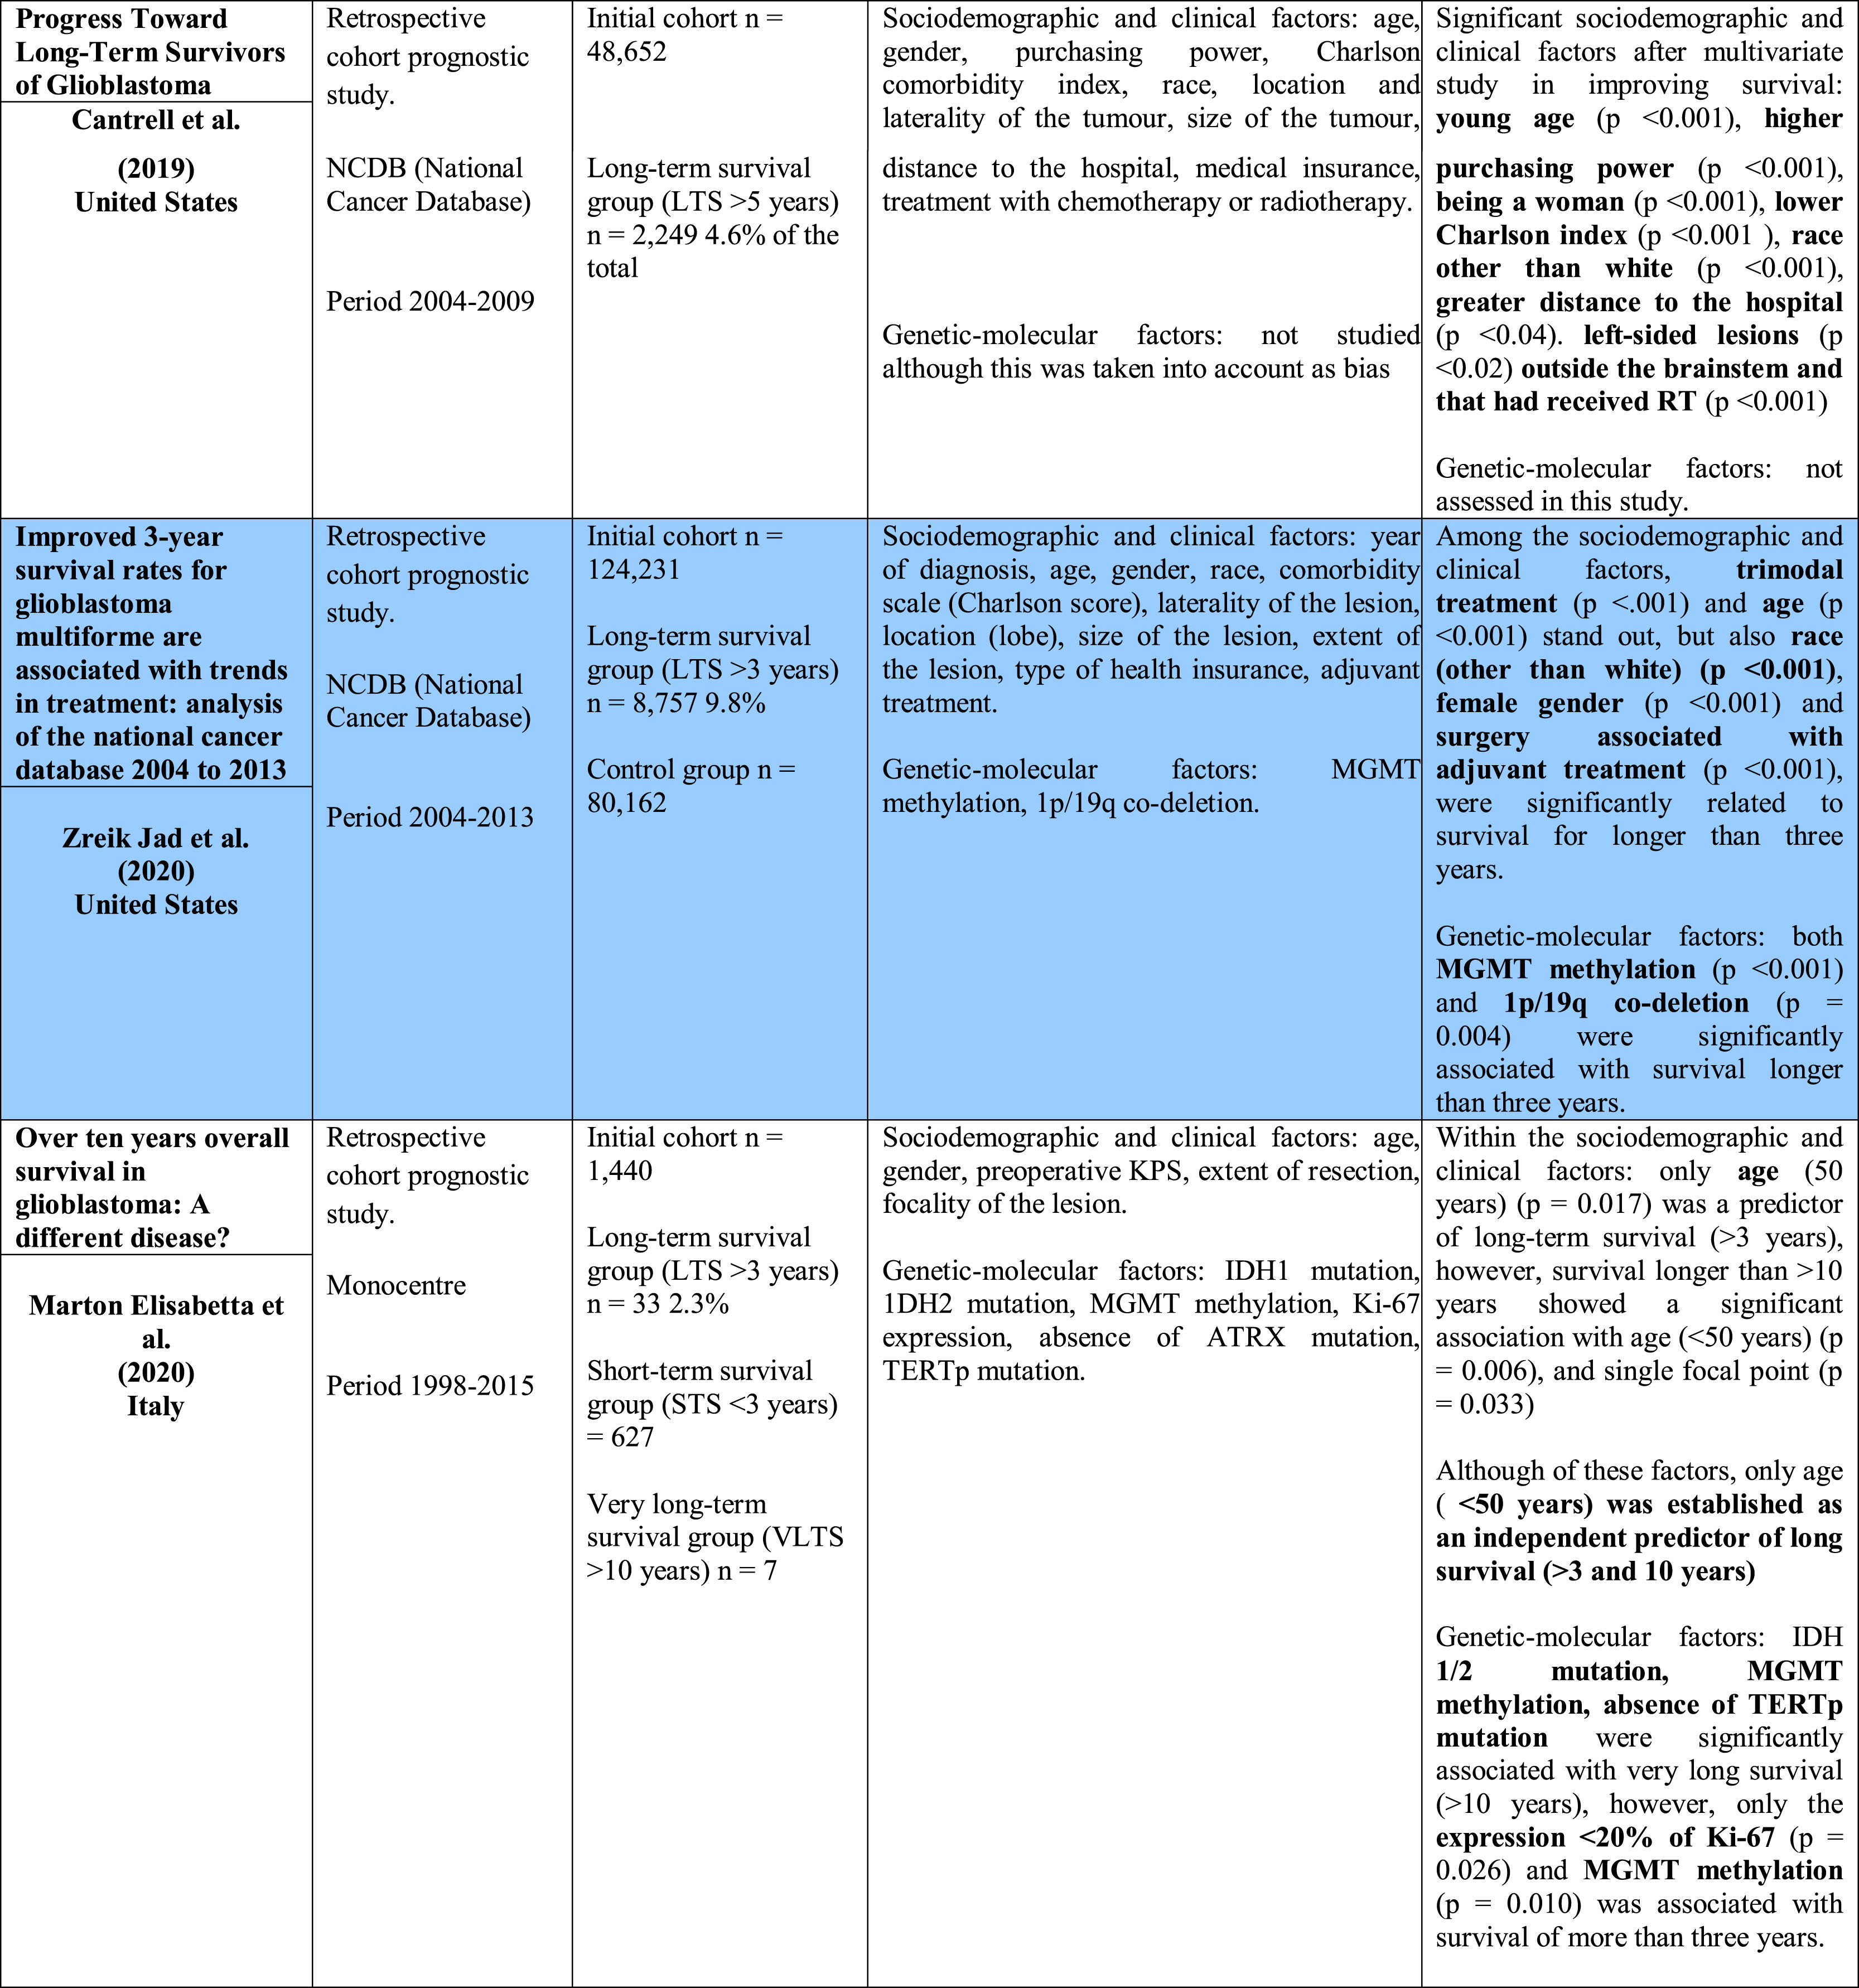

In spite of the changes for the treatment of glioblastoma since 2005, we have not seen differences between long-survival patients of more than 10 years showing a value minor than 1%.

Material and methodWe realize a systematic analysis and identify important factors for long survivor patients. We also show an own case with more of 20 years of survival. We make a new pathological study of the old paraffin block of this patient.

ResultsThe most important variable associated with long-survival between all multivariant studies is the age. When we try to find genetic and molecular alterations in glioblastoma associated with prolongated survival, the MGMT promoter methylation play the most important role. We find a correct diagnosis in the current analysis of our patient’s sample with very long survival.

ConclusionsMultiple variables are found that affect long survival of glioblastoma series but analyzed studies are very heterogeneous and it is very difficult comparation between them. Most articles we review are obtained from databases of different countries with hundreds of patients. It would be very interesting to promote the use of a single database in Spain that allows us to study these long-term glioblastoma survivors.